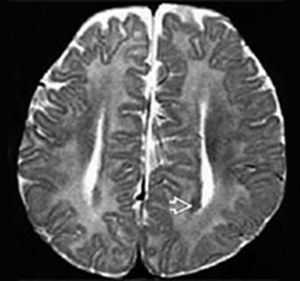

Характерным анатомическим изменением является колпоцефалия, при которой расширены задние отделы боковых церебральных желудочков. Состояние не относится к истинной гидроцефалии новорожденных, а обусловлено уменьшением кортикальных ассоциативных путей. Еще один типичный признак порока — пучки Пробста, представляющие собой неправильно ориентированные аксоны, расположенные параллельно межполушарной щели.

- КТ головного мозга. При компьютерной томографии определяются широко расставленные передние рога, высокое стояние третьего желудочка, параллельный ход медиальных стенок боковых желудочков. КТ производится в рамках постнатальной диагностики.

- МРТ головного мозга. Для максимально точной визуализации степени агенезии или гипоплазии мозолистого тела новорожденным выполняется магнитно-резонансная томография в трех плоскостях. По показаниям МРТ может рекомендоваться беременным женщинам для исключения несовместимых с жизнью сочетанных пороков ЦНС.